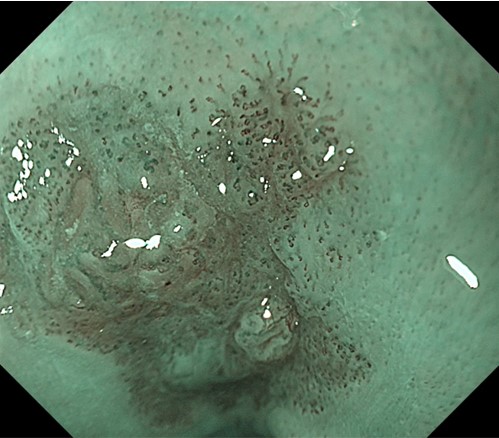

High-magnification NBI (1)

Assessment of IPCLs is possible with high-quality images in NBI observation at high magnification. Images with very little blur can be obtained, which makes possible IPCL observation with high accuracy. The “tetrad criteria” of IPCLs, namely, dilation, tortuosity change in caliber, and various shapes, can be confirmed.

High-magnification NBI (2)

Assessment of IPCLs is possible with high-quality images in NBI observation at high magnification. Images with very little blur can be obtained, which makes possible IPCL observation with high accuracy. Here, abnormal vessels that do not show a loop-like formation can be clearly recognized. High-magnification NBI is considered optimal for invasion depth analysis.